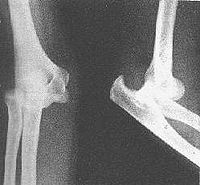

影像学表现

肱骨远端与桡、尺骨近端的关节对位关系发生分离。以肱骨远端为标准点,桡尺骨近端向后上方移位为后脱位,向前下方移位为前脱位,向侧方移位为侧方脱位。以肘关节后脱位为最常见。

3.X线检查 肘关节正侧位片可显示脱位类型、合并骨折情况,并与髁上骨折相区别。